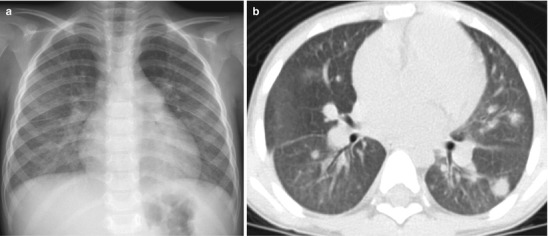

Lymphadenopathy (present in 92 %) with or without a visible Ghon focus is the radiographic hallmark of TB infection and usually involves the hilar and paratracheal regions. The Ghon focus may be too small to be radiographically visible but can also undergo caseation and calcify (Fig. 13.17). Disease progression may occur at the site of Ghon focus, within the regional lymph nodes, or following disease spread (Fig. 13.18). Parenchymal involvement in primary pulmonary TB most commonly appears as homogeneous consolidation, although it can appear patchy, linear, nodular, and mass-like. Caseation necrosis, liquefaction, or calcifications can be seen within the consolidation and can progress into extensive lung damage (Marais et al. 2004) (Fig. 13.19). Enlarged and edematous hilar, paratracheal, and subcarinal lymph nodes may cause compression of the adjacent bronchus and can lead to hyperinflation or atelectasis of the affected lung segment. Contrast-enhanced CT shows a characteristic appearance consisting of central areas of low attenuation with peripheral rim enhancement and obliteration of perinodal fat (Kim et al. 1997) (Fig. 13.20).

Fig. 13.18.

Primary TB disease. Chest radiographs of a 2-year-old girl with chronic cough and fever showing dense right middle lobe consolidation on the frontal view (a) and extensive lymphadenopathy (white arrows) on the lateral view (b)